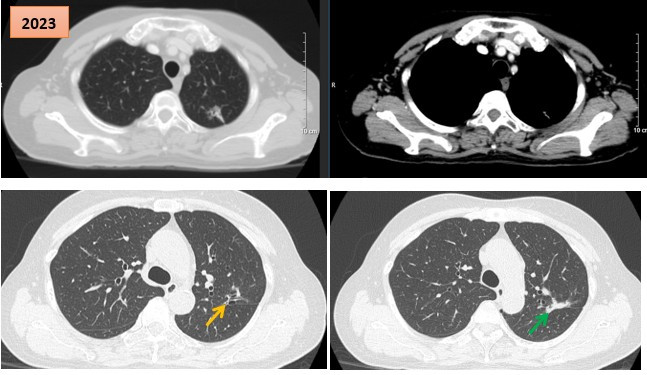

Hình ảnh cắt lớp vi tính theo dõi trong quá trình điều trị, tổn thương xơ hóa tại vị trí u cũ (mũi tên xanh) và giãn khu trú các nhánh phế quản liền kề (mũi tên vàng).

Kết quả chụp CT ngực-bụng và cộng hưởng từ sọ não không ghi nhận thêm tổn thương mới. Tại vị trí u cũ, tổn thương xơ hóa gây co kéo rãnh liên thùy và giãn khu trú các nhánh phế quản lân cận, song không ảnh hưởng đến chức năng hô hấp và không gây triệu chứng lâm sàng.